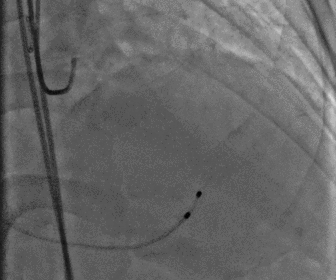

股动脉造影

图片